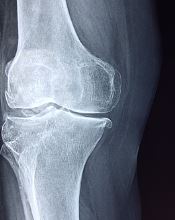

무릎 연골 손상 증상으로 어딘가 불안정한 느낌이 들고, 붓고, 통증이 지속적으로 있다면 반드시 필요한 치료를 받아야 합니다.

지금까지 무릎 연골 손상 증상에 대해 알아보았습니다. 연골은 한 번 손상되면 다시 재생되지 않습니다. 손상정도를 최대한 방지하는 것이 중요하고, 많이 손상되었다면 적극적으로 치료해야하고, 그 상태가 심각하다면 수술도 고려해야 합니다.

그러니 조금이라도 통증이 발생한다면 바로 병원으로 달려가 진료를 받는 것이 매우 중요하니 참고하시기 바랍니다.